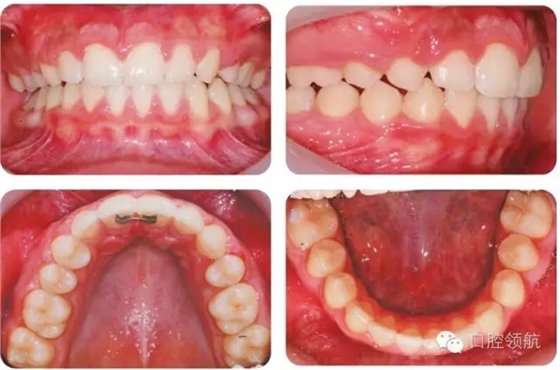

UR4應如何改形模擬UR3?

UR4改形受到休息和功能狀態(tài)時上唇位置和上前牙外觀影響。休息時上唇線較低,切緣暴露很少,這樣齦緣高度不一致的情況不必特別考慮。因為第一前磨牙近遠中徑小于尖牙,托槽應略靠遠中使牙齒近中腭側旋轉。為了使前磨牙伸長,托槽應放置在臨床牙冠中心略偏齦方,使頰尖位置與對側尖牙協調。如果伸長前磨牙導致咬合早接觸,應適當降低舌尖。如果笑線較高,應考慮壓入第一前磨牙或外科修整齦緣高度。前磨牙可以進行貼面以更好地模擬尖牙外觀,調整牙尖垂直位置。圖2.45為最后的咬合像。